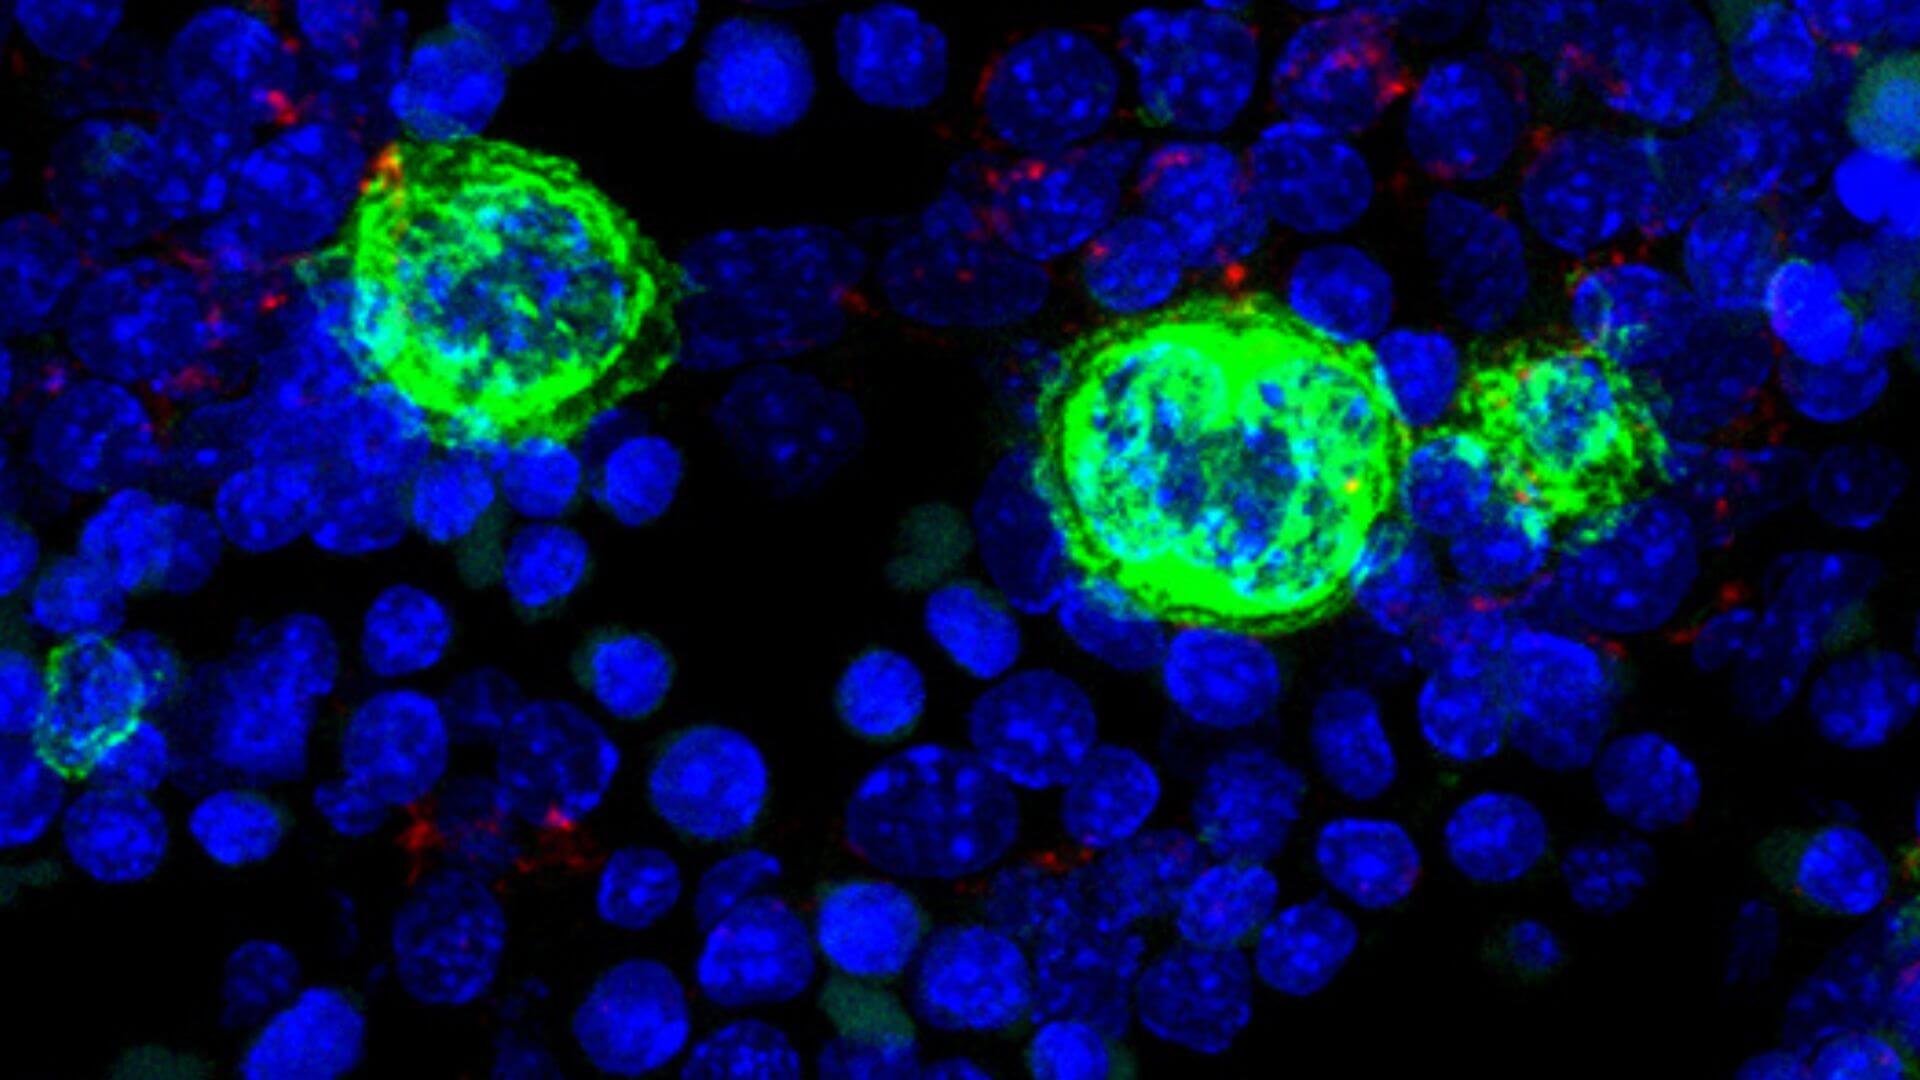

Una de estas células que encontramos en la médula ósea roja es el megacariocito, una célula con unas características muy particulares y de la que seguimos aprendiendo a día de hoy muchas cosas. Además de por su gran tamaño, como ya hemos comentado anteriormente, los megacariocitos se caracterizan por tener un núcleo poliploide (con más de 2 copias de cromosomas). Para conseguir un núcleo de este tipo los megacariocitos sufren un proceso conocido como endomitosis, que consiste en duplicar el material genético sin separar el citoplasma celular (la mayoría de las células después de la mitosis o división del material genético sufren la división del citoplasma o cariocinesis). La endomitosis consigue dar lugar a una célula enorme con un núcleo también de mayor tamaño y contenido genético. Las diferentes etapas que atraviesa el megacariocito, desde la célula hematopoyética madre en la médula ósea (HSC, de sus siglas en inglés hematopoietic stem cell), pasando por diferentes estadios de maduración que podemos diferenciar por su morfología y tamaño, se conoce como megacariopoyesis. En el caso de los humanos este proceso tarda 5-7 días (Imagen 1)

Un hecho relevante en la biología de los megacariocitos es que estas células, junto con los eritrocitos, se generan durante el desarrollo embrionario en la primera onda de diferenciación hematopoyética o hematopoyesis primitiva. Este hecho enfatiza la importancia de estas células y de sus productos: las plaquetas (también llamadas trombocitos) desde el inicio de la vida y en la mayoría de las especies de animales. Estudios realizados en el laboratorio de Inmunobiología del Centro Nacional de Microbiología (ISCIII) han demostrado la importancia de los megacariocitos durante la hematopoyesis en el hígado fetal (órgano que mantiene este proceso en la mitad de la gestación previamente a que la médula ósea adquiera este importante papel). Los megacariocitos embrionarios contactan con las células hepáticas para favorecer su mantenimiento y maduración e interactúan a través del receptor VEGF-A (Hepatology, 2012). Además estos megacariocitos embrionarios tienen algunas características diferenciales con los megacariocitos del individuo adulto como por ejemplo la ausencia de expresión del receptor CD45, una proteína conocida como pan-hematopoyética (Haematologica, 2019). (Imagen 2)